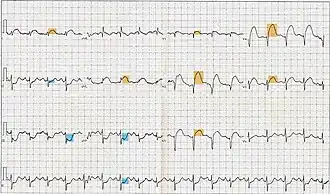

Acute coronary syndromes are classified to two major categories, according to the patient's electrocardiogram, and specifically the presence or absence of persistent (>20 min) ST segment elevation (or left bundle branch block).[2] Patients with acute coronary syndrome and ST elevation are said to have ST-elevation myocardial infarction (STEMI) and they tend to have one of their coronary arteries totally blocked.[3] Damage is reversible for approximately 20[4]-30[5] minutes after complete obstruction of blood flow; thereafter myocardial cell death ensues and progresses as time passes. Therefore, complete and sustained restoration of blood flow must be as prompt as possible to ensure maximum salvage of functional myocardium, a principle expressed in the maxim "time is muscle".[6] This is achieved with reperfusion therapy, which is based on invasive reopening of the affected coronary artery with primary percutaneous coronary intervention, or non-invasive breaking up of the responsible blood clot with a thrombolytic drug.[7]

In patients with symptoms typical of myocardial ischemia an electrocardiogram must be immediately obtained - e.g., within 10 minutes from first contact with medical or paramedical personnel, including prehospital setting; the electrocardiographic findings will guide the subsequent management. Patients with elevation of the ST segment (or presumed new left bundle branch block) are treated based on guidelines for ST elevation myocardial infarction (STEMI) and must undergo reperfusion therapy as soon as possible. Serum cardiac biomarkers are routinely obtained and their elevation is necessary for confirming diagnosis of myocardial infarction;[27] however, reperfusion must not be delayed by waiting for the results. Patients without the above findings are initially classified with non ST elevation acute coronary syndrome, and subsequent cardiac biomarker results will differentiate between true non ST elevation myocardial infarction (NSTEMI) and unstable angina.[28][29][30]